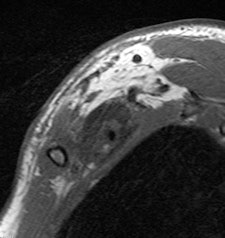

Patients ranged in age from 18 to 84 years. Their lesions detected by MRI represented a mix, including 35 root avulsions and brachial plexus cord injuries, 22 primary or secondary tumors, and four each entrapment syndromes, fibrous scars, and Parsonage-Turner syndrome.

Overall, the sensitivity for the total number of examinations analyzed on a per-patient basis was 81% and specificity was 91%. Analyzed by findings, mass lesions had the highest positive predictive value at 95%, followed by traumatic injury at 91%. The lowest was for entrapment syndromes, at 80% and 66% for post-treatment evaluation. Negative predictive values ranged from a low of 83% for traumatic injury to a high of 2% for mass lesions and post-treatment evaluations.